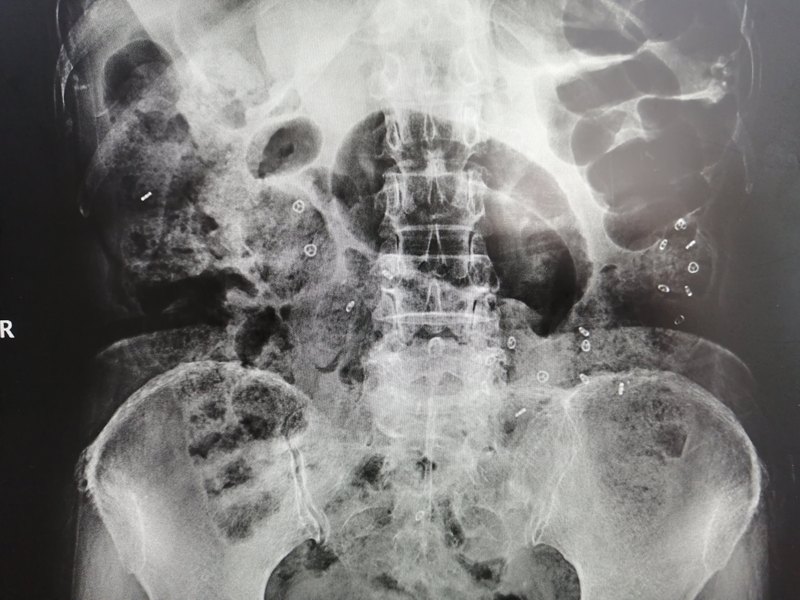

患者,女,因頑固性便秘,之前行回腸直腸吻合術(shù),病變結(jié)腸給予了保留,術(shù)后癥狀無(wú)任何改善,門(mén)診收入院后給予完善的便秘相關(guān)檢查,行結(jié)腸傳輸試驗(yàn)、排糞造影、腸鏡檢查,診斷為混合型便秘(慢傳輸型便秘,直腸前突),腸鏡可見(jiàn)第一次手術(shù)情況,見(jiàn)下圖。 故昨天在全麻下行腹腔鏡下全結(jié)腸切除術(shù)+直腸前突修補(bǔ)術(shù)

昨日?qǐng)F(tuán)隊(duì)為一例頑固性便秘術(shù)后的患者再行手術(shù),該女性患者2018年因頑固性便秘在上海某知名三甲醫(yī)院行回腸直腸吻合術(shù),術(shù)后便秘癥狀無(wú)改善,上周就診于全應(yīng)軍主任專家門(mén)診,初步評(píng)估為頑固性結(jié)腸慢傳輸便秘,此前手術(shù)僅行回直腸吻合,并沒(méi)有起到結(jié)腸曠置的效果。 收住院,行結(jié)腸傳輸試驗(yàn)、排糞造影、腸鏡檢查全面評(píng)估。結(jié)腸傳輸試驗(yàn)發(fā)現(xiàn)經(jīng)過(guò)72小時(shí)全部粒子滯留在橫結(jié)腸和降結(jié)腸,慢傳輸便秘診斷明確。排糞造影提示直腸前突25mm,出口梗阻性便秘亦存在。此患者考慮為混合型便秘。腸鏡檢查明確上次外院手術(shù)為回腸和直腸側(cè)側(cè)吻合,結(jié)腸黑病變。腸鏡距肛門(mén)20cm見(jiàn)結(jié)腸回腸吻合口。 全應(yīng)軍主任分析病情認(rèn)為回腸直腸吻合治療便秘僅適合年老體弱患者,此患者六十多歲,一般情況良好,首次手術(shù)吻合方式并不解決便秘,需要更徹底的手術(shù)。 8月14日全麻下行腹腔鏡全結(jié)腸切除術(shù)+直腸前突經(jīng)肛修補(bǔ)術(shù),手術(shù)切除全部傳輸慢的結(jié)腸,連同原手術(shù)的吻合口,徹底解決慢傳輸和出口梗阻便秘。該患者年輕的時(shí)候因血吸蟲(chóng)脾腫大做過(guò)開(kāi)腹脾臟切除術(shù),加之18年的回直腸吻合術(shù),腹腔存在比較嚴(yán)重的粘連,但手術(shù)團(tuán)隊(duì)仍然嫻熟的在腹腔鏡下完成整個(gè)手術(shù)操作。腹腔鏡微創(chuàng)手術(shù),僅僅通過(guò)肚子上幾個(gè)小孔就完成,術(shù)后患者恢復(fù)順利,今日術(shù)后第一天患者即可下床活動(dòng)。